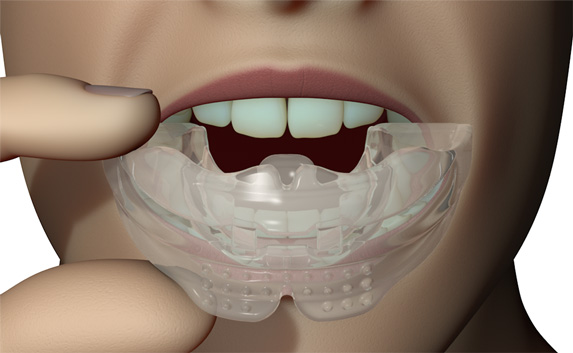

The Myosa® for TMJBDS® S3 is used in the third and final stage of treatment, when the patient's Breath Hold Time (BHT) has reached 45 seconds or more. The S3 is primarily designed to finalise the establishment of nasal breathing, while improving breathing and myofunctional disorders. The S3 can also serve as a transition appliance between the first and second phase of TMJBDS® treatment, involving arch development in combination with the Myobrace® appliances. It is for this reason that the S3 is a derivative of the Myobrace®A1 appliance.